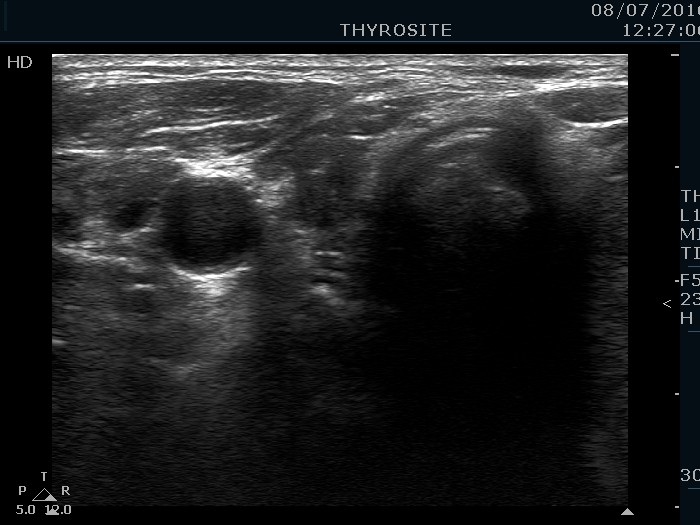

Ultrasonography. The thyroid was echonormal. There was a hypoechoic nodule in the right lobe. The nodule presented all three signs of a possible extrathyroidal extension. A large, mixed nodule occupied almost the entire left lobe. This lesion had back wall cystic figures and microcalcifications, too. The intranodular vascularization was increased.

1. Such large nodules are difficult to examine and difficult to present in images.

2. The left lobe clearly presented microcalcifications in the solid part.